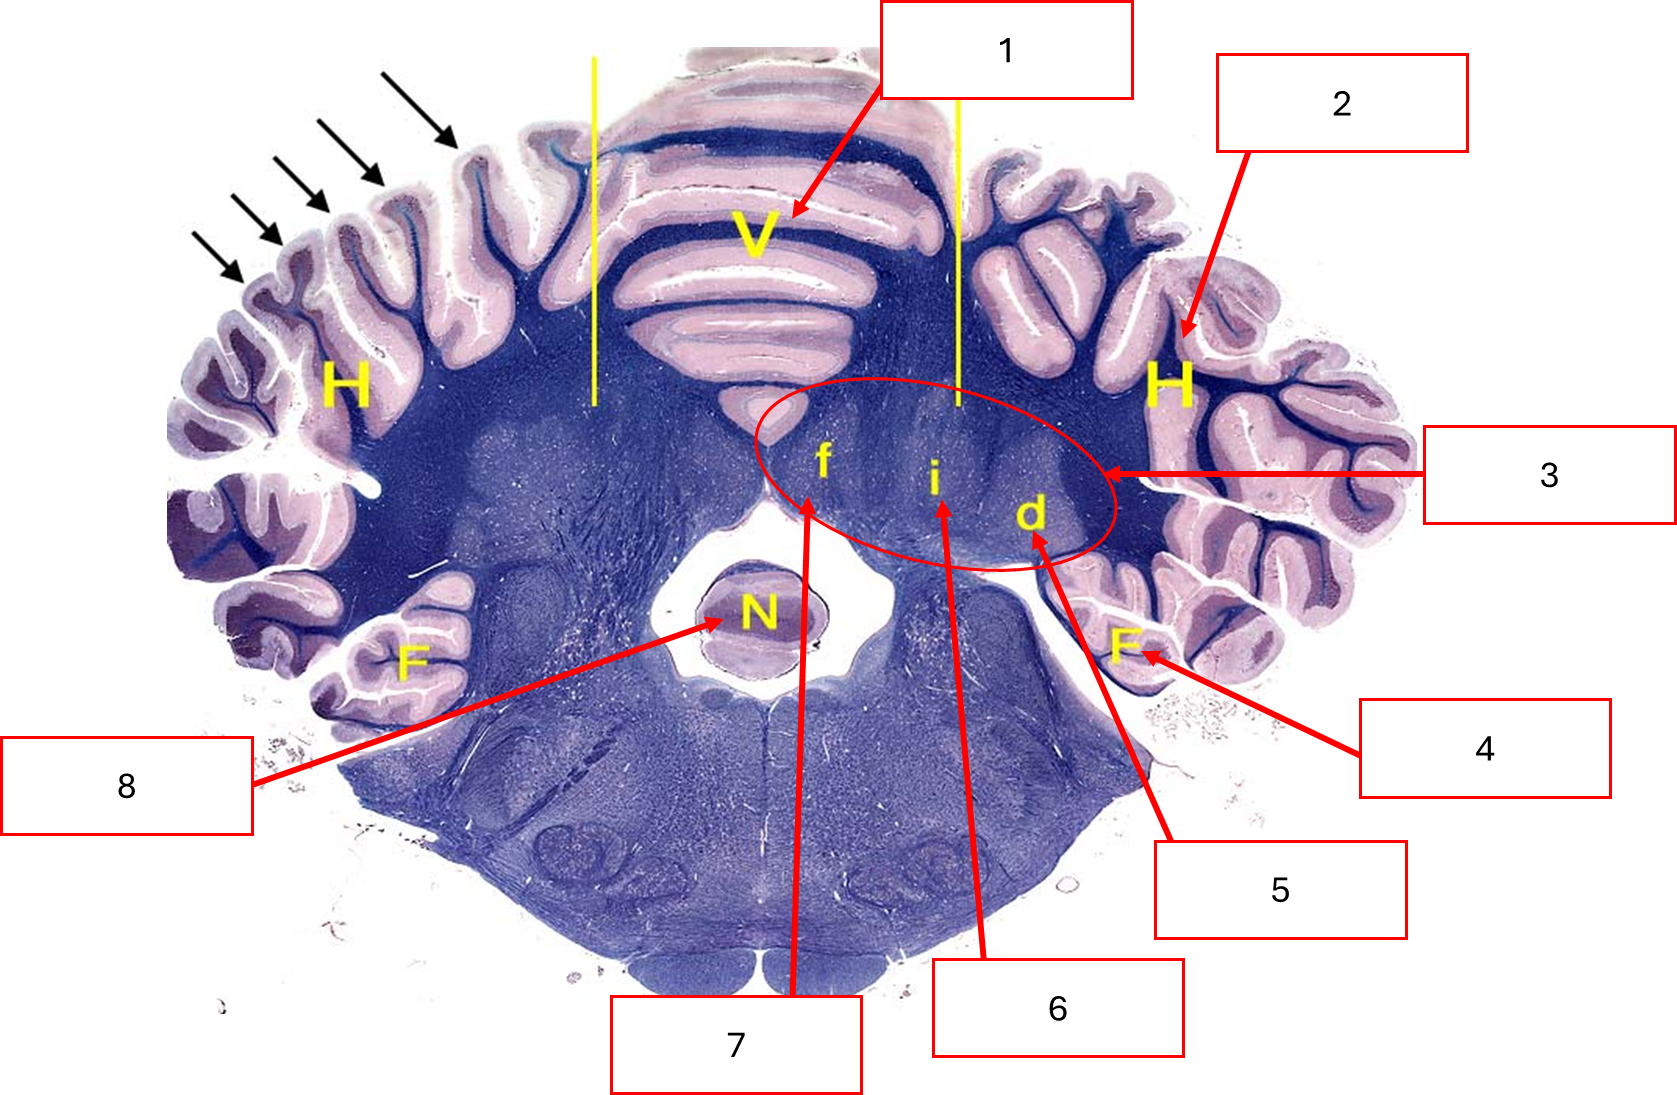

Histo ของ diencephalon

Corpus callosum

Interventricular foramen

Interthalamic adhesion

Third ventricle

Optic chiasm

Hypothalamus

Thalamus

Internal capsule

Lateral ventricle